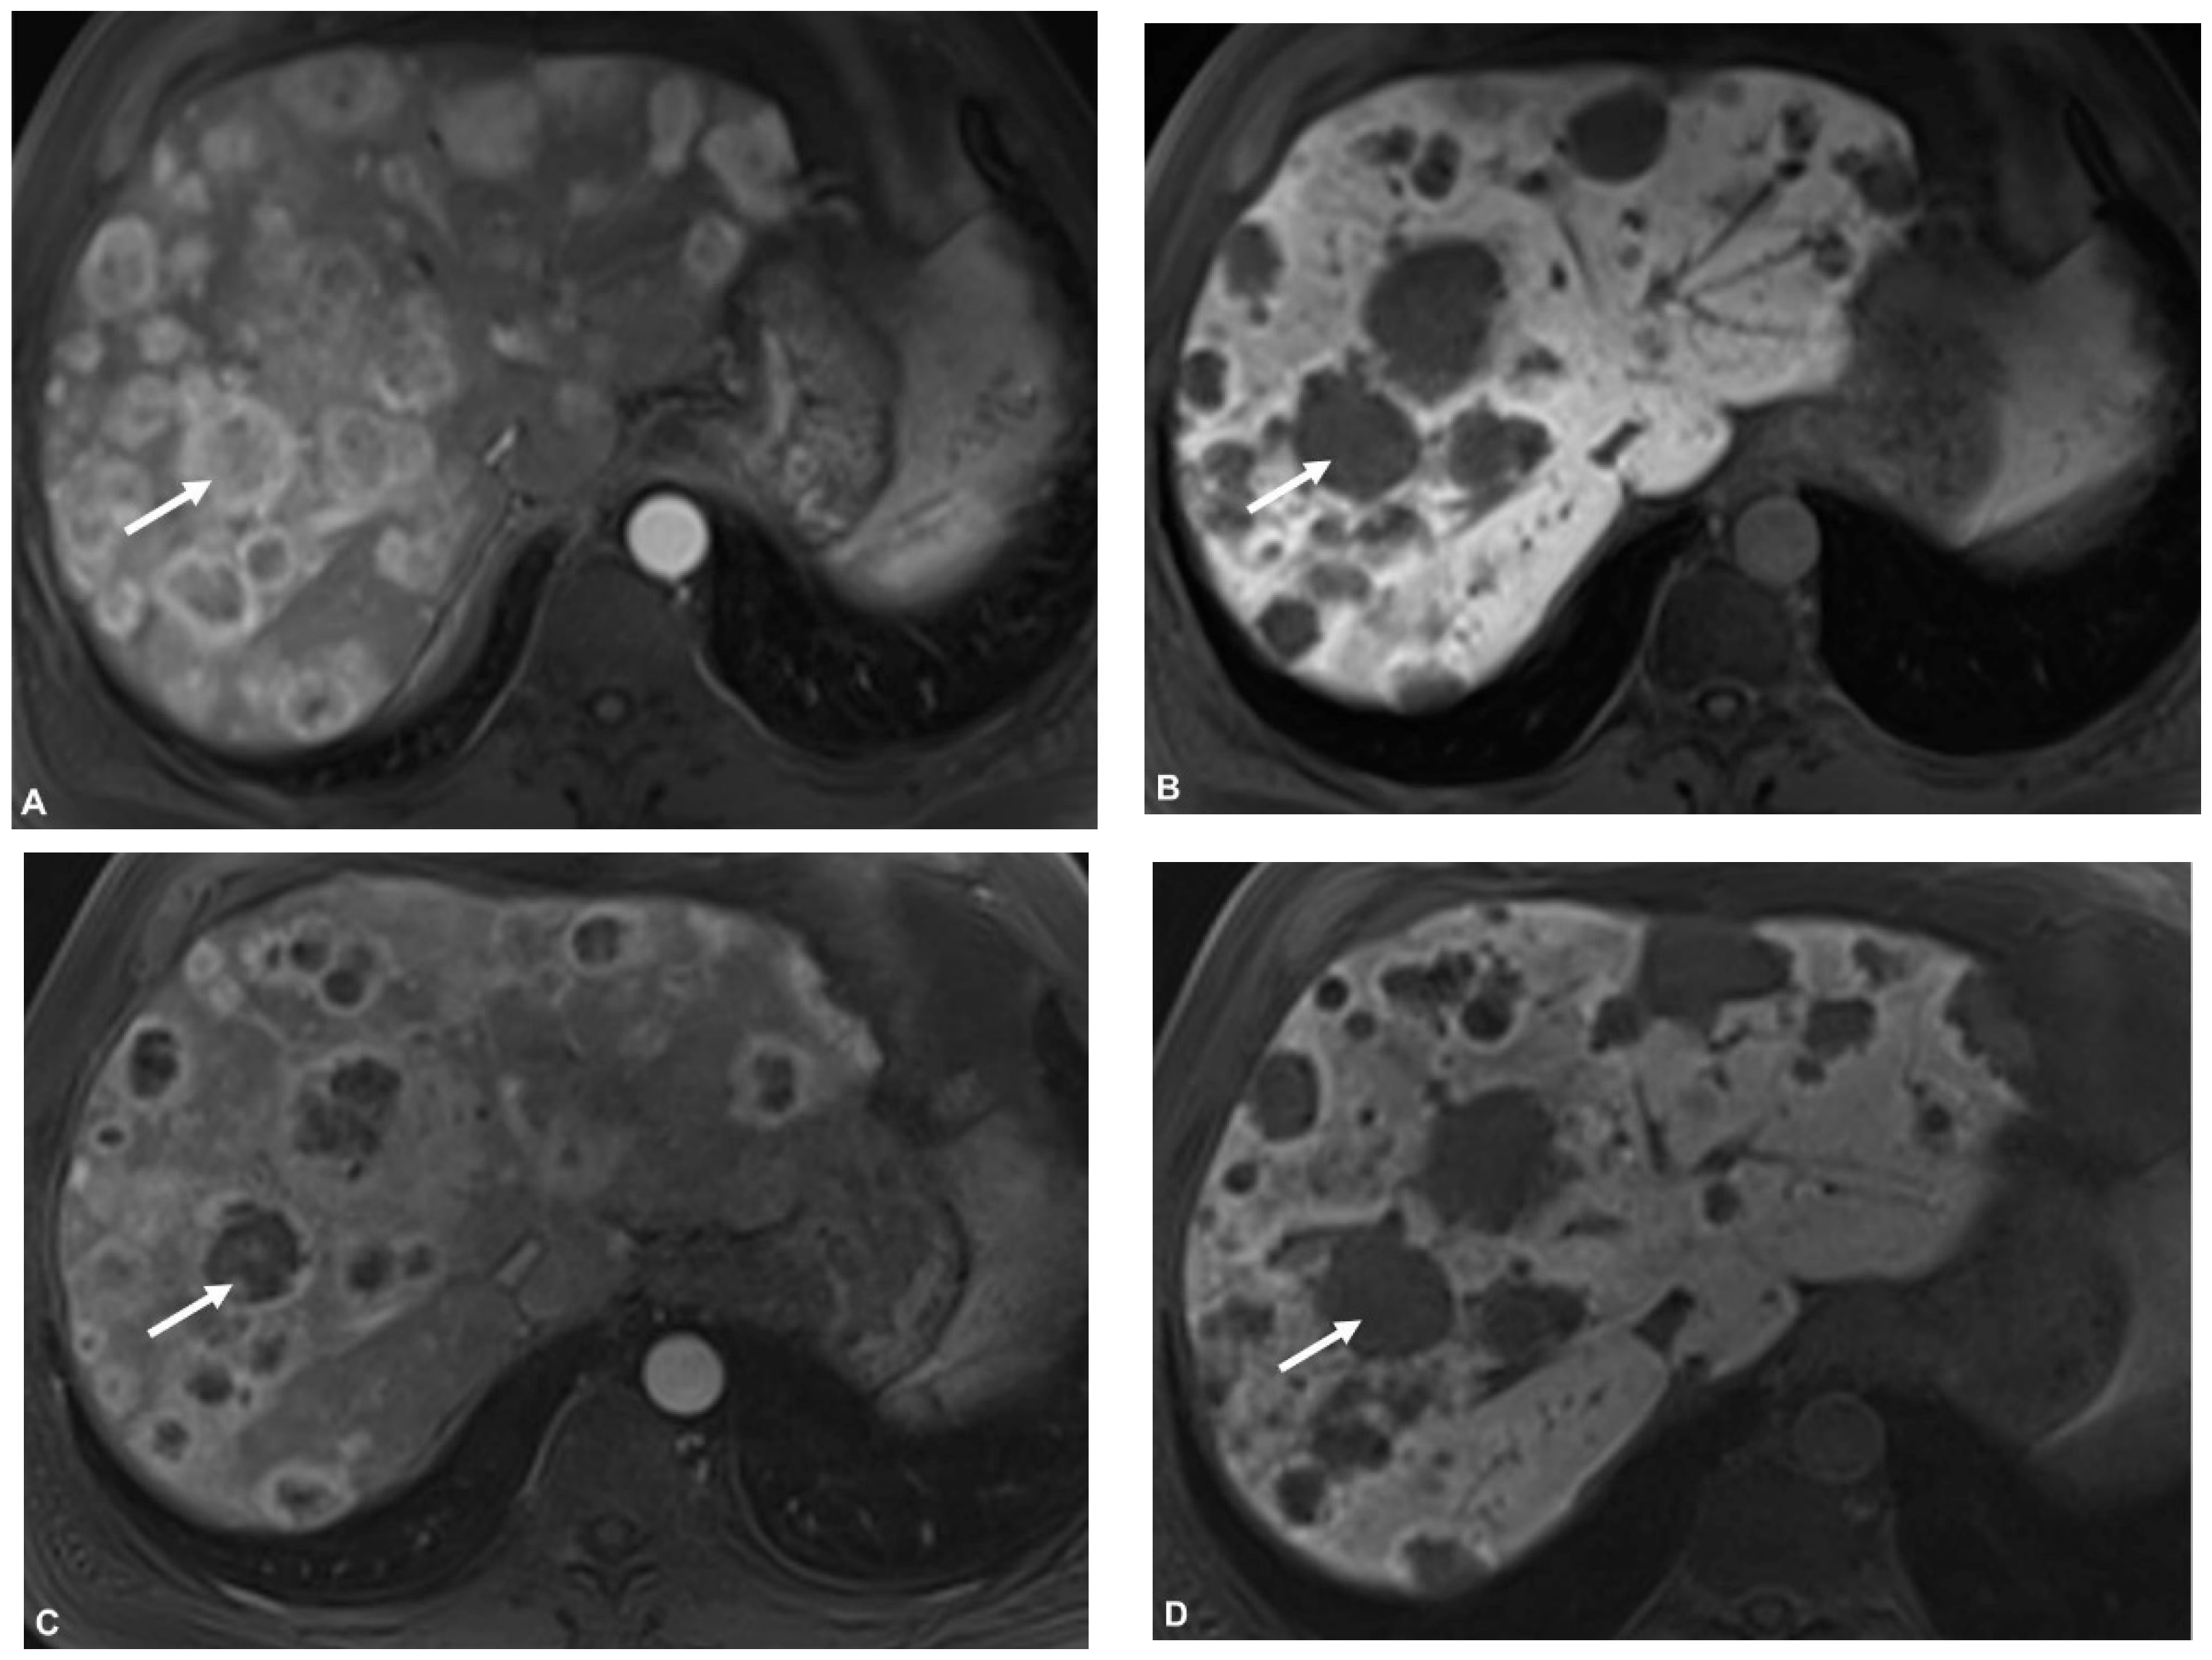

2.3. MR Imaging

2.4. PET/CT

2.5. Image Analysis

3.2. Pre- and Postinterventional Measurements